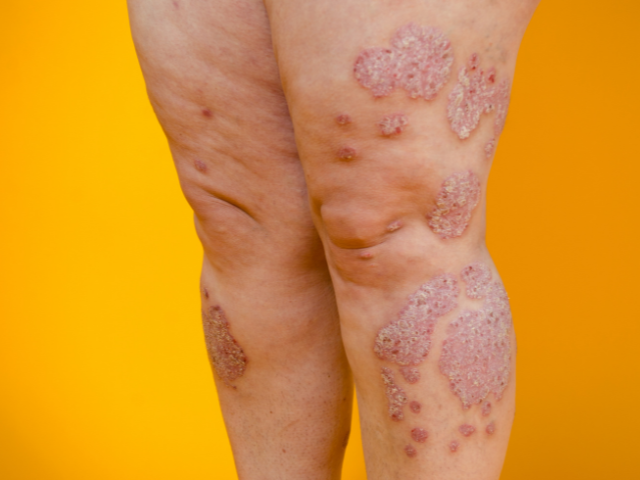

ZoomOur five-part workshop series on inflammatory skin diseases, kicks off with 'Diagnosing and Treating Common Nail Disorders'. This workshop provides GPs and GP registrars an opportunity to upskill in assessing and managing a variety of nail conditions.